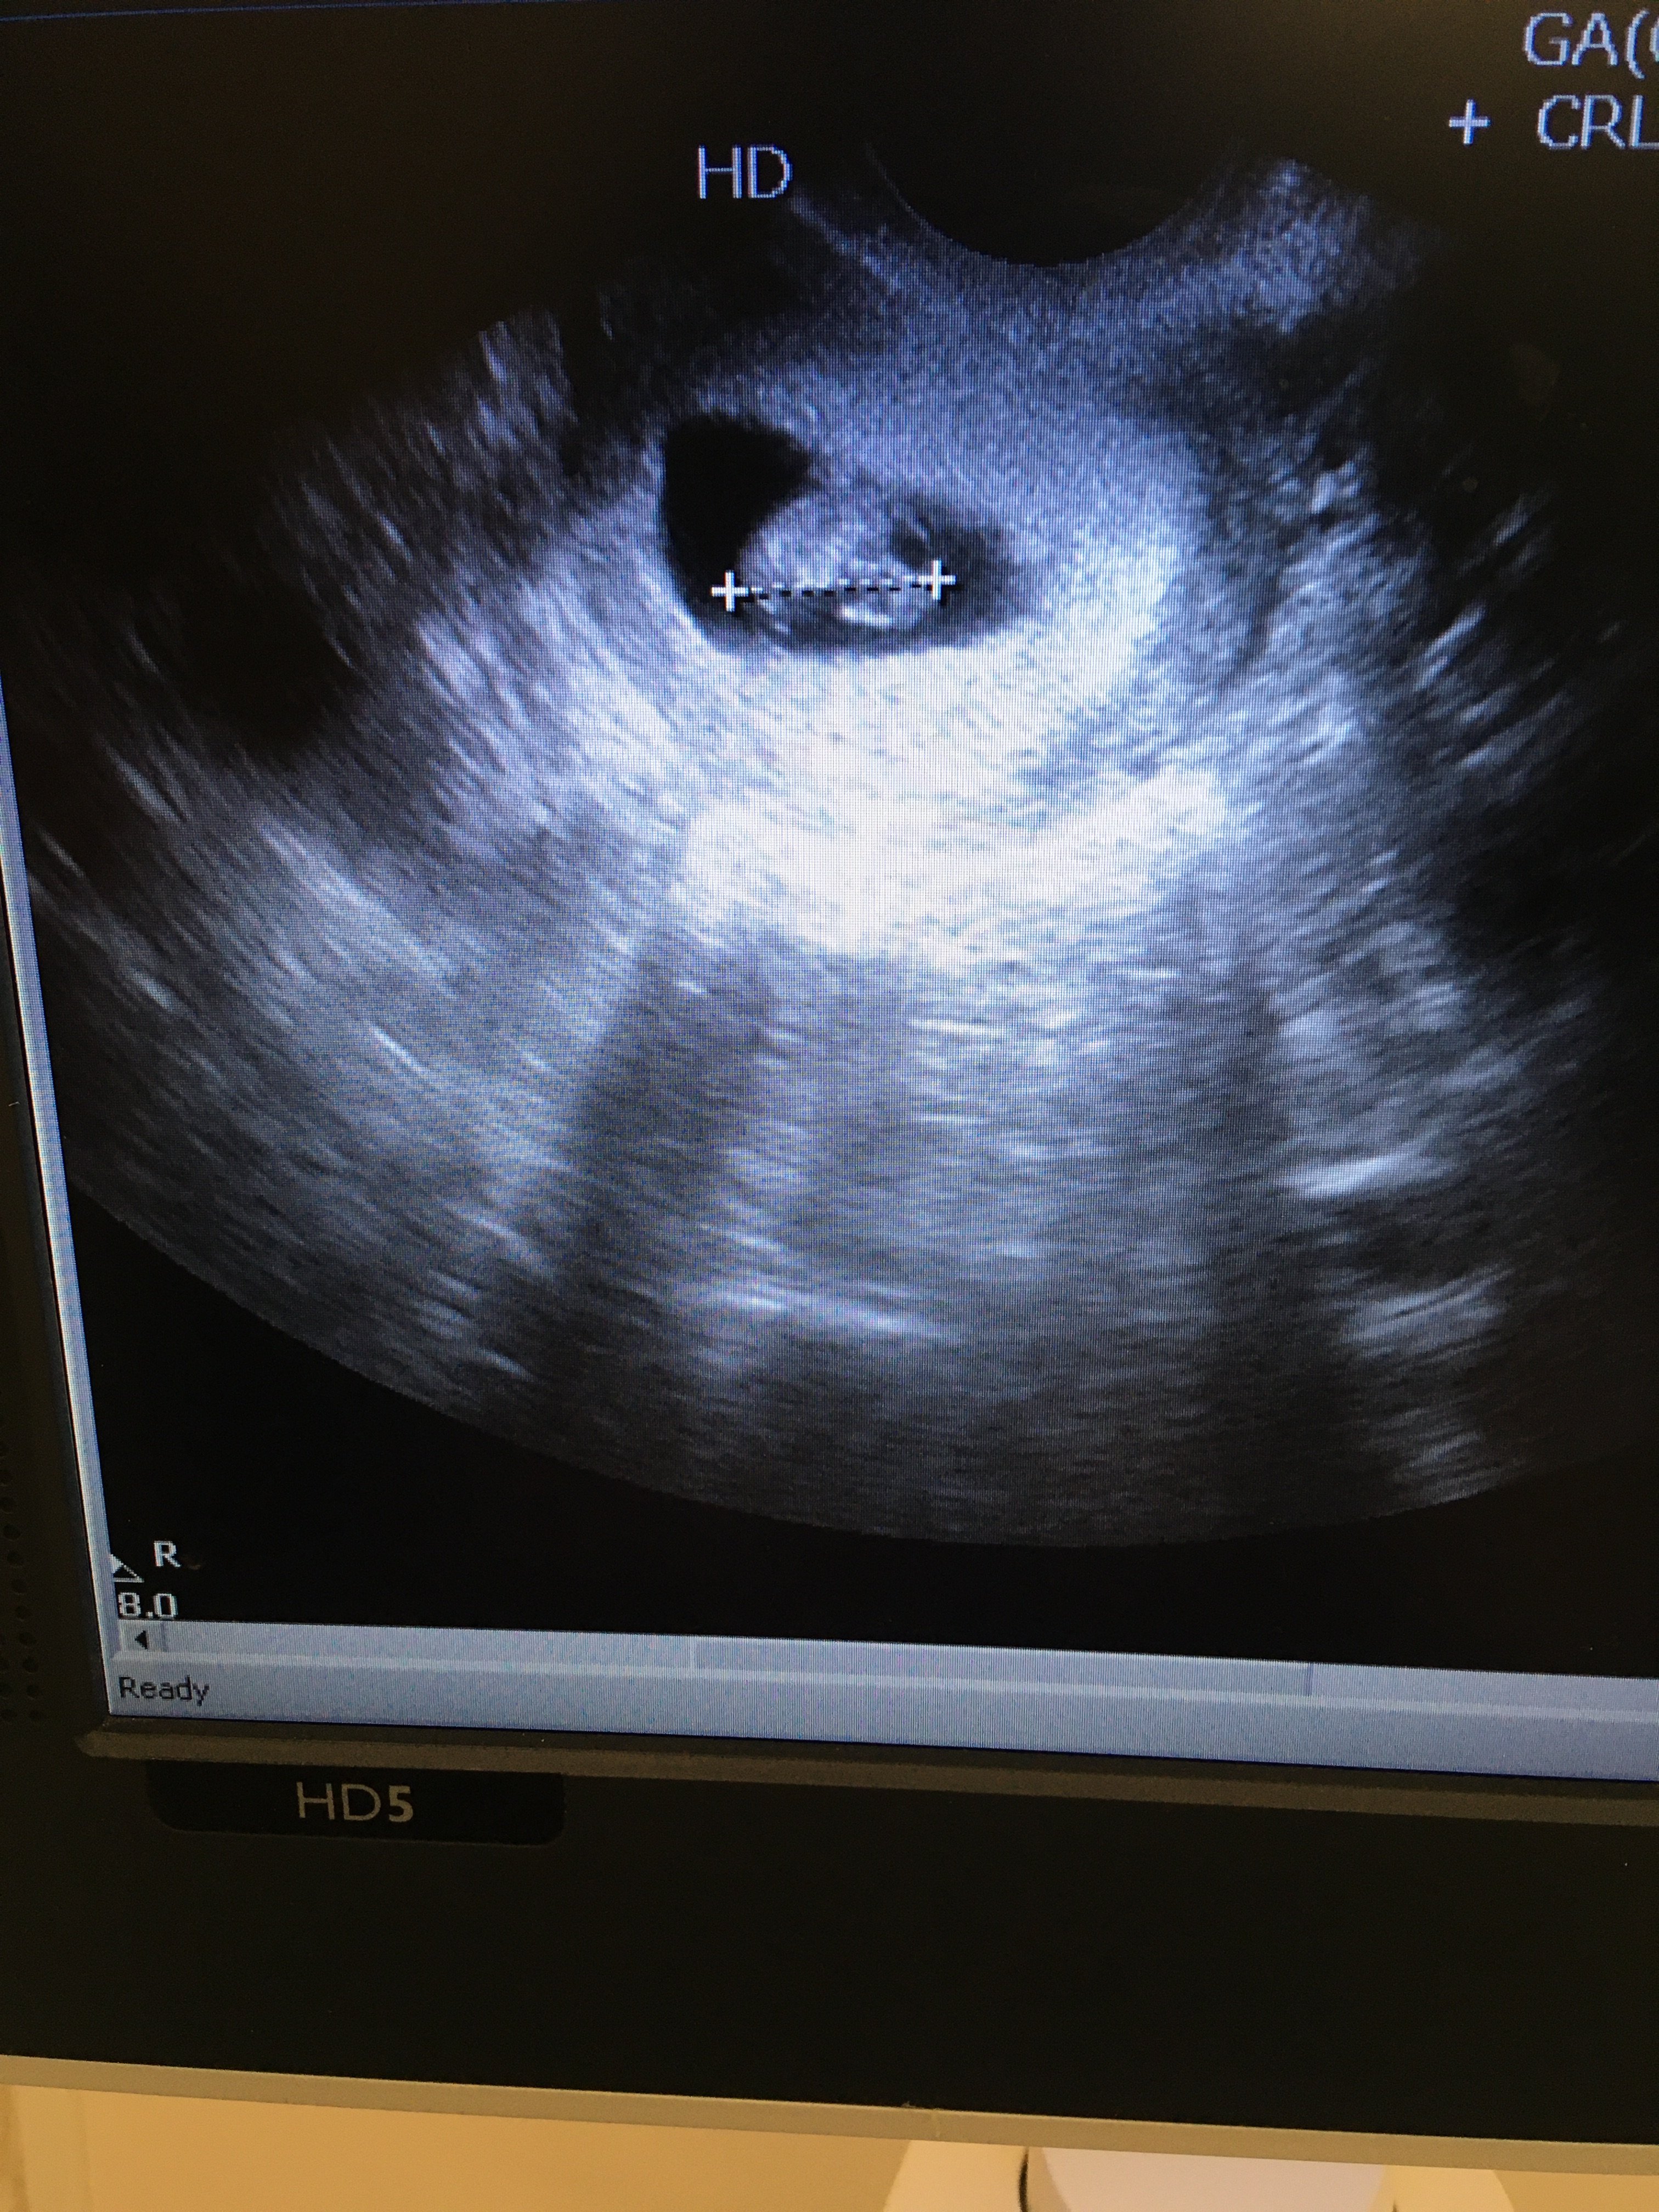

Hej dziewczyny , na początku chce Wam Bardzo podziękować za słowa otuchy co do mojego ostatniego postu o mdłosciach i moim psychicznym załamaniu przez niego. Jak wiecie mieszkam w Grecji i tu trochę inaczej jest z lekarzami. Tak wiec dziś miałam pierwsze usg i cytologia. Serduszko bije♥️ , według ostatniej miesiączki 8tc , z usg 7+3. Oczywiście zrobiło mi się słabo podczas badania 🤭, ale szybko wróciłam do siebie. Także bardziej mąż emocjonalnie zaragował na obraz i dziwek bijącego serduszka , ja już czułam , że lekko odpływam. Na szczęście nie straciłam przytomności tylko było mi słabo i oblało mnie potem. No, ale tak to jest jak mdłości mam cały czas i mało jem.

Teraz czy dała mi coś na mdłości , w sumie nie chciała , powiedziała że dają tylko jak już kobieta nie może nawet wody pić i ciagle wymiotuje. Natomiast coś tam przepisała i kazała brać tylko w ostateczności. Druga sprawa , moja opryszczka/ zimno na brodzie. Nic mi nie dała na to , żadnej maści i chyba nie wiedziała co to jest ( witaj w Grecji ). Za dwa tygodnie zaś mam wizytę. Natomiast zalecone badania będę miała na kartce dopiero w piątek. W piątek mąż ma podskoczyć i odebrać kartkę jakie badania mam zrobić. Dziękuje Wam bardzo za wsparcie jakie mi dajecie , pani doktor powiedziała tylko ,że jeszcze miesiąc i mi minie. No , ale może pomogą tabletki od niej bo ja nawet na zewnątrz nie wychodzę. Aaaaa i nie ma podanego terminu porodu 😜, a ja z tego Wszystkiego nie zapytałam , ale z aplikacji wychodzi 18 sierpień plus/ minus 2 tygodnie zawsze się robi. Miłego dnia